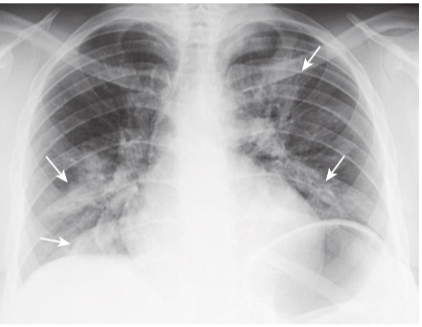

Staphylococcal bronchopneumonia.

There are multiple irregularly marginated patches of airspace disease in both lungs (white arrows). This is a characteristic distribution and appearance of bronchopneumonia. The disease is spread centrifugally via the tracheobronchial tree to many foci in the lung at the same time, and so it frequently involves several segments. Because lung segments are not bound by fissures, the margins of segmental pneumonias tend to be fluffy and indistinct. There are no air bronchograms present because inflammatory exudate fills the bronchi and the airspaces around them.